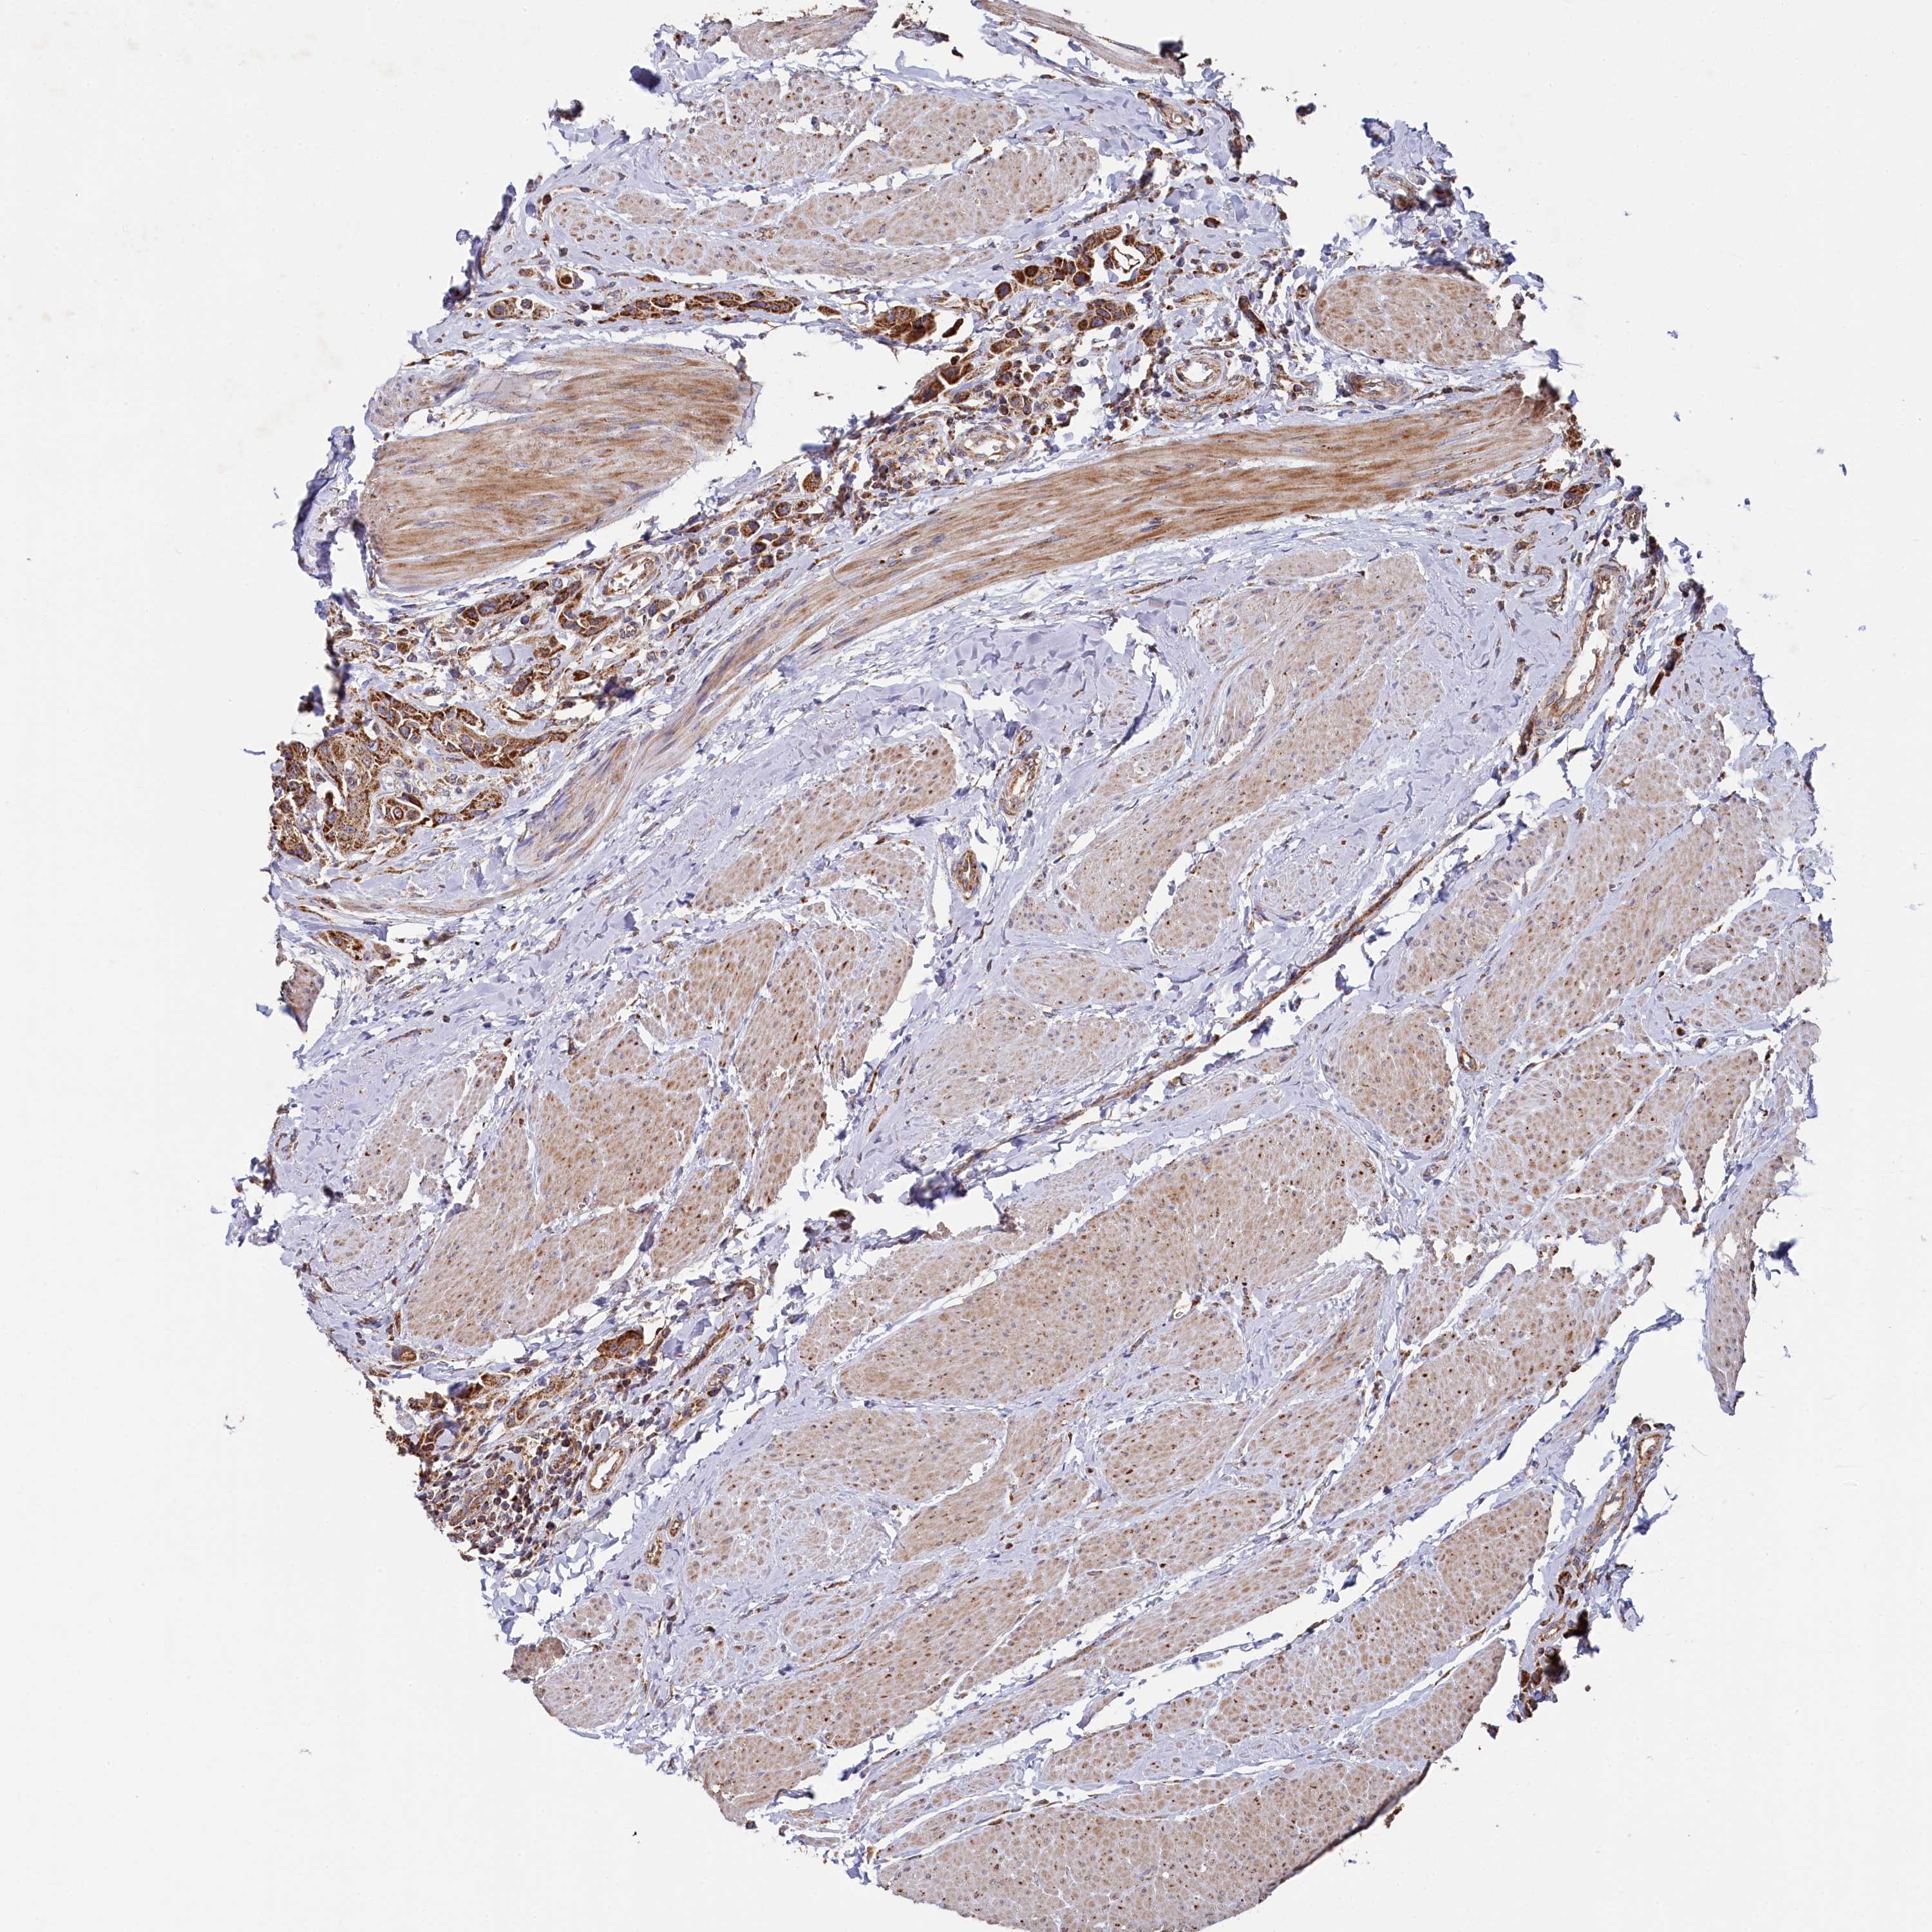

UROTHELIAL CANCER - Protein expressioni

A mouse-over function shows sample information and annotation data. Click on an image to view it in a full screen mode. Samples can be filtered based on level of antibody staining by selecting one or several of the following categories: high, medium, low and not detected. The assay and annotation is described here.

Note that samples used for immunohistochemistry by the Human Protein Atlas do not correspond to samples in the TCGA dataset.

Antibody stainingi

Antibody staining in the annotated cell types in the current human tissue is reported as not detected, low, medium, or high, based on conventional immunohistochemistry profiling in selected tissues. This score is based on the combination of the staining intensity and fraction of stained cells.

Each image is clickable and will lead to virtual microscopy that enables deeper exploration of all samples and also displays staining intensity scores, fraction scores and subcellular localization as well as patient and tissue information for each sample.

Antibody HPA039965

Staining

High

Medium

Low

Not detected

Intensity

Strong

Moderate

Weak

Negative

Quantity

>75%

75%-25%

<25%

None

Location

Nuclear

Cytoplasmic/membranous

Cytoplasmic/membranous,nuclear

Urothelial carcinoma, High grade

Urothelial carcinoma, Low grade